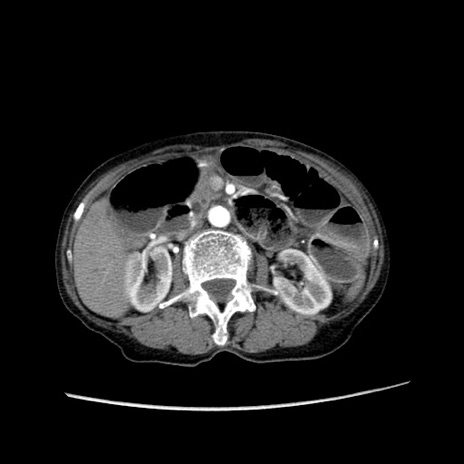

症例25(横断像)

【症例】80歳代女性

【主訴】胸のつかえ感

【現病歴】約9時間前に食後から胸のつかえた感じあり、嘔吐あり、来院。

【既往歴】胃癌(全摘)、胆摘、虫垂炎

【身体所見】心窩部に圧痛あり、反跳痛なし。

【データ】WBC 5700、CRP 0.05